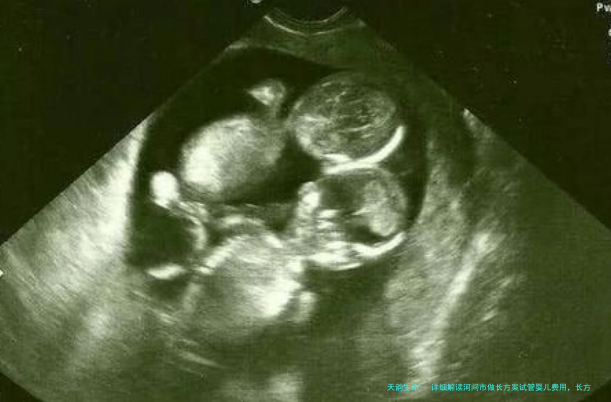

试管三十五天能做肚子彩超吗?B超检查时间和寓意